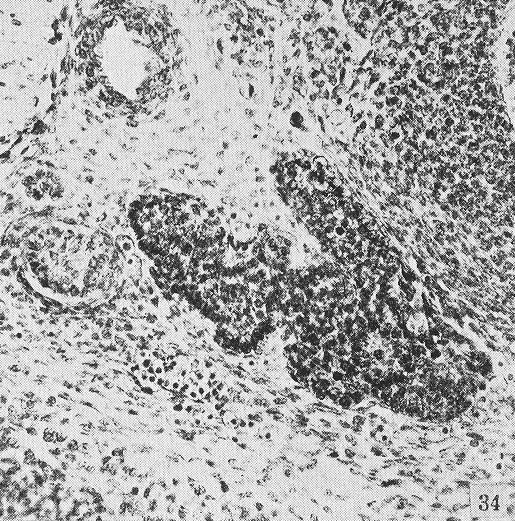

Transverse section of the median thyroid of embryo number 4430. A portion of the pharynx is shown in the upper right corner of the figure.

Weller, 1933.